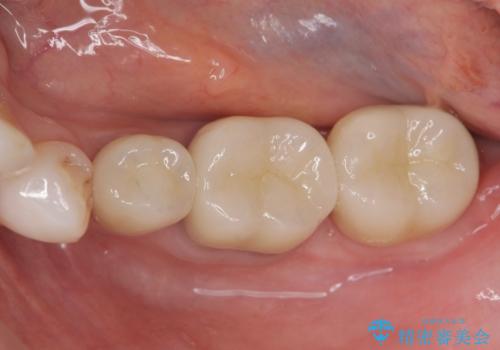

歯周外科で達成する、安定したクラウン周囲の歯肉環境

歯ぐきの腫れを改善する歯周外科手術を伴うセラミック治療